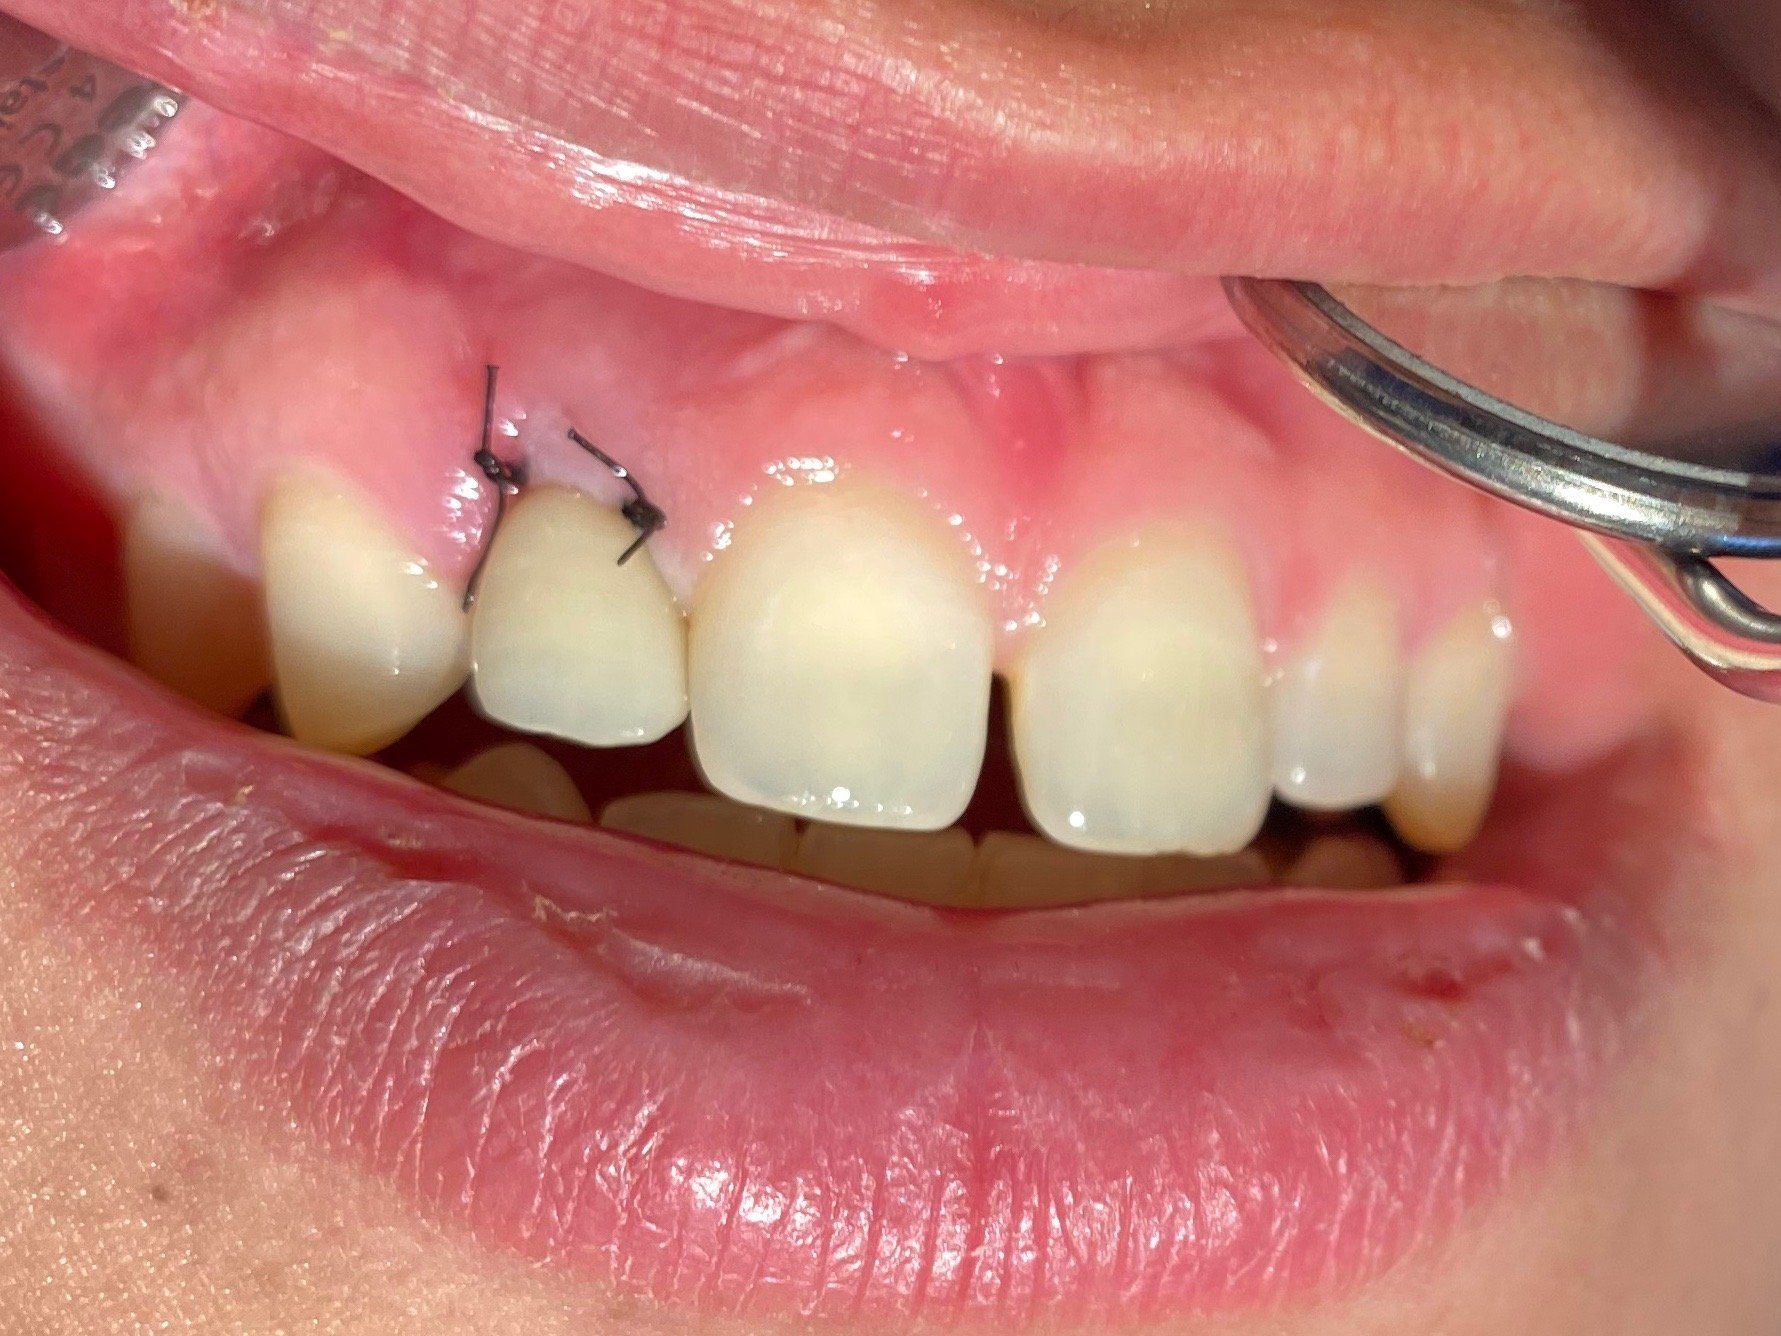

Fall 1:

Nach atraumatischer Extraktion und Kontrolle der buccalen Knochenwand erfolgt die palatinal positionierte Aufbereitung und Implantation. Mit intraoperativem Drehmomentprotokoll erfolgt die Platzierung des BLX Implantats mit einem Drehmoment größer als 35 N/cm.